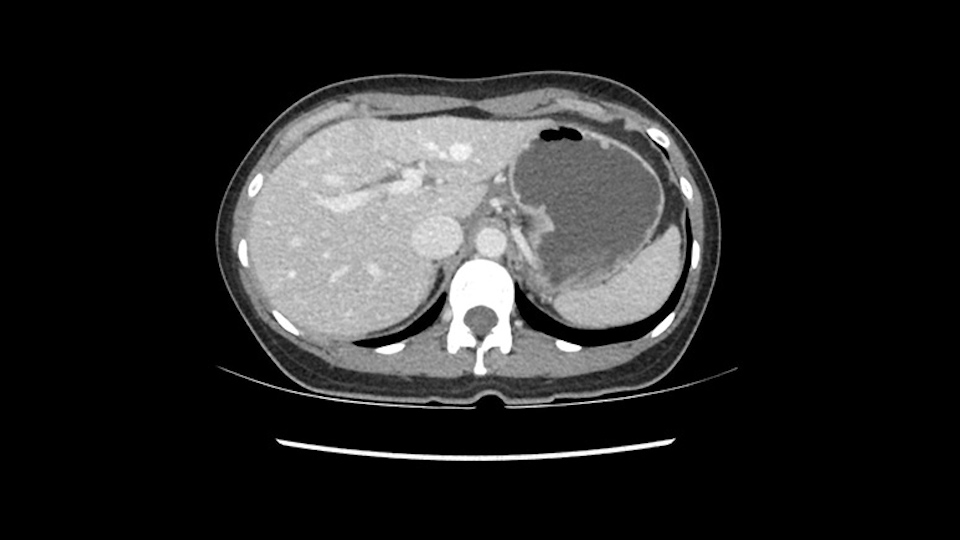

So if we look at the CT scan, on the axial, it’s a larger lesion. It’s about 6 or 7 or 8 centimeters. So it does look a bit threatening in terms of its resectability but if you really drill down deeply into the anatomy, and I think the coronal [imaging] is even better, you can see that the entire mass is on the patient’s left side of the falciform ligament. So it’s really only a left-sided tumor and not even really a left-sided tumor because Segment 4 is uninvolved anatomically.

As I review the CT scan, we have both arterial and venous phases, the tumor is obvious. But I’ll start by saying that the liver itself does not appear to be cirrhotic to my eye. It’s got a normal contour and allied to that, that I do not see evidence of portal hypertension. The spleen is normal, there’s no collateral vessels. The tumor itself, I measured maximally at about 11 centimetres in diameter and I’m told the alpha fetoprotein is very high (over 10000), which is entirely consistent with this being a solitary hepatocellular carcinoma that is very exophytic. It seems to emanate off the inferior margin of Segment 3 (because that’s the falciform). I’ll start by saying that this is not transplantable. The tumor exceeds our guidelines for transplantation, but it's likely resectable based on normal liver and no portal hypertension.

When you see the axial sections of the scan, you find it's a largely exophytic mass and its well-encapsulated. So this is typically true of a well-differentiated hepatocellular carcinoma. If you look at this, this is the gallbladder which is being displaced to the right and the mass is in the Sg4 of the liver, exophytic, projecting down. As it is coming down, it is also displacing the duodenum and the head of the pancreas which is being pushed towards the left and it's going right up to the cava, the start of the anterior surface of the cava. Obviously getting a lot of collaterals and vascularity from all the vessels around but one has to be very careful in evaluation of the main portal pedicle in this particular case and of course arterial inflow to the Sg4 and of course the left lobe of the liver.

So in planning for this operation, as I look at the scans, I first visualize the arterial phase and I can see that there’s are a lot of big feeding arteries to this large tumor. Likely all the right side vessels feeding the right side of the liver: right hepatic artery and likely the Segment 4 artery are spared from the tumor. It’s likely the left hepatic artery is ramificating and giving feeding arteries to this tumor. It certainly looks like a large mass that its compressing other structures like the cava, the pancreas, the stomach; but I think there’s a plane and we can see that better in the venous phase. There’s a plane of separation between the gallbladder, the pancreas, the cava, that this tumor is abrupting but likely not invading. Usually, these masses actually don’t invade at that level and basically are pushing the tissues and once you open, you’re able to separate the tumor. Sometimes there’s some adhesions but you can actually separate and there’s usually no invasion.